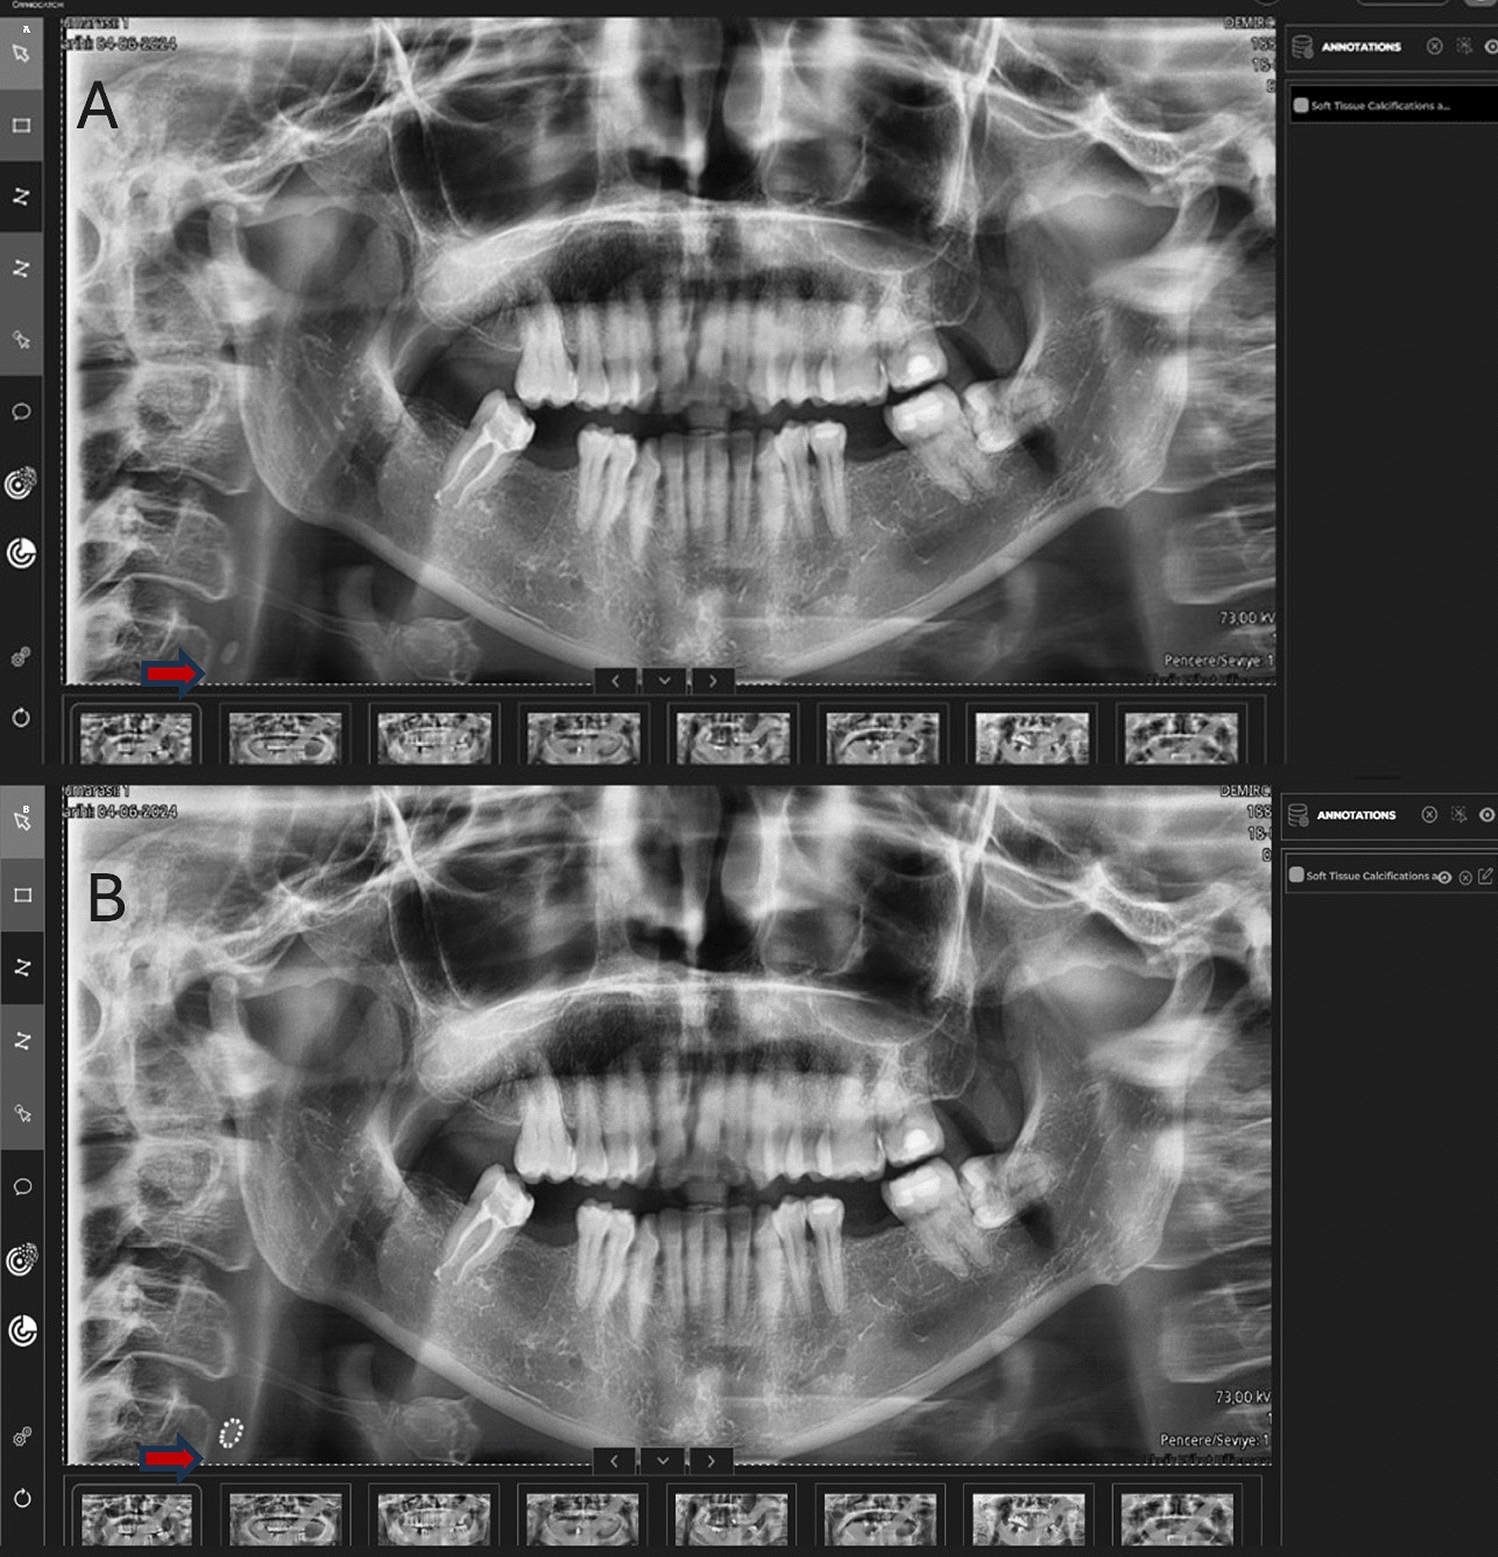

Casazza E, Ballester B, Philip-Alliez C, Raskin A. Evaluation of mandibular bone density in bruxers: the value of panoramic radiographs. Oral Radiol. 2023;39(1):117–24. https://doi.org/10.1007/s11282-022-00612-3.

Eninanc I, YalcinYeler D, Cinar Z. Investigation of mandibular fractal dimension on digital panoramic radiographs in bruxist individuals. Oral Surg Oral Med Oral Pathol Oral Radiol. 2021;131(5):600–9. https://doi.org/10.1016/j.oooo.2021.01.017.

Unal Erzurumlu Z, Sadik E, Gokkurt BN, Ozbey F, Erzurumlu K, Kasko Arici Y. Morphological evaluation of gonial and antegonial regions in bruxers on panoramic radiographic images. BMC Oral Health. 2023;23(1):457. https://doi.org/10.1186/s12903-023-03162-0.

Casazza E, Ballester B, Siaud B, Philip-Alliez C, Raskin A. Relationship between bruxism and mandibular bone modifications based on medical imaging: a scoping review. BMC Oral Health. 2023;23(1):483. https://doi.org/10.1186/s12903-023-03209-2.